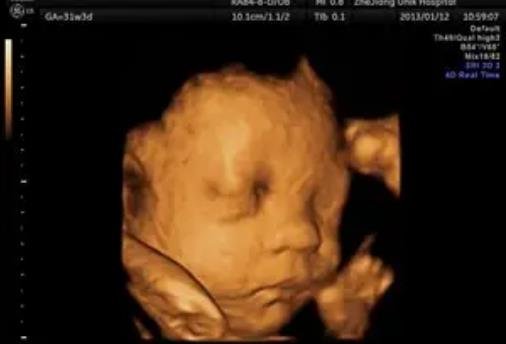

雖然懷孕的時(shí)候醫生是絕對不會(huì )告訴家長(cháng)胎兒性別的,但大多數家長(cháng)還是按捺不住好奇心,總想自己從各種檢查單子上看出男女差異。網(wǎng)上一直流傳懷女孩的標志是圓形的孕囊,要是B超單有這個(gè)一般是女孩,那么現實(shí)真是這樣嗎?除了孕囊還有別的懷女孩標志嗎?下面小編就帶大家來(lái)了解一下。

1、圓形的孕囊:B超單上可以看到孕囊,要是孕囊是長(cháng)形的,那么就是男孩,要是孕囊呈圓形或橢圓,那可能就是女孩。

2、較高的胎心率:女寶寶的胎心率一般在150以上,而男寶寶的胎心率一般在140左右。

3、背朝外的胎位:這是由很多孕媽發(fā)現的規律,女孩子喜歡背朝外,面朝里,姿勢很像在和媽媽擁抱一樣。

4、雙頂徑和股骨的差小于2:雙頂徑是胎兒頭部的橫向長(cháng),而股骨則是胎兒大腿骨的長(cháng)度,由于男女體型差異,女孩子的頭和腿的差異很小,一般都會(huì )小于2。

以上就是網(wǎng)上流傳的生女孩的標志,但只要生過(guò)孩子的人都知道,這其實(shí)一點(diǎn)科學(xué)依據都沒(méi)有,只是為了滿(mǎn)足寶爸寶媽的好奇心而已,大家看看就行,不要當真,最重要的還是胎兒的健康發(fā)育。